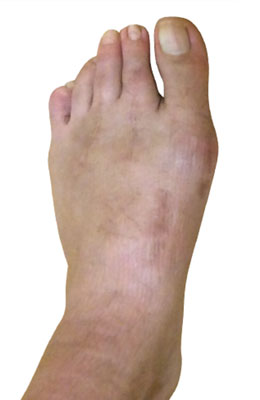

Before

Lapidus Forever Bunionectomy™ and Hammertoe Correction before

After

Lapidus Forever Bunionectomy™ and Hammertoe Correction after

Lapidus Forever Bunionectomy™ and Hammertoe Correction

George is a 62-year-old businessman who presented with a sore on his second toe from rubbing on his shoes. We decided to correct his foot as a whole and performed several orthopedic surgical procedures as she had both types of bunions. He chose our Lapidus Forever Bunionectomy™, a hammertoe correction and an osteotomy for his Tailor’s Bunion (bunionette). George was weight bearing on his foot at two weeks and back in regular shoes at 8 weeks with no pain and full function.